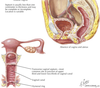

A

ovary

65

ovary

66

ectopic pregnancy

67

ectopic pregnancy

68

ectopic pregnancy